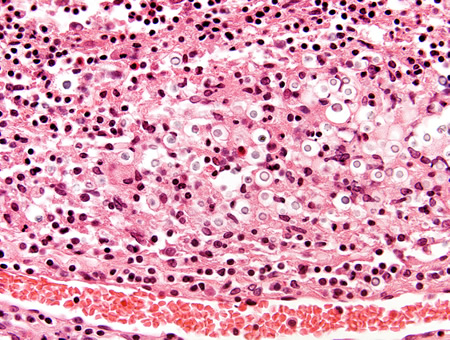

Biópsia do cérebro de um paciente imunocompetente com meningite criptocócica exibindo meninges com células inflamatórias e Cryptococcus

Do acervo pessoal de Robert E. Schmidt; usado com permissão